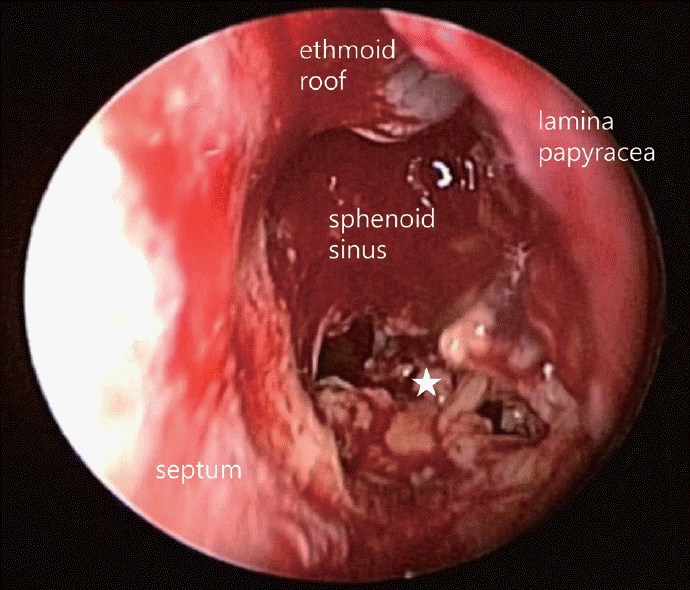

환자의 증상 및 영상소견을 종합하여 접형동을 침범한 악성종양을 의심하여 치료계획을 수립하기 위해 수술적 조직검사를 계획하였다. 영상학적 검사상 종괴가 시신경의 해부학적 주행과 인접하게 위치하여, 전신마취하에 수술을 시행하였으며, 부비동내시경 수술을 통해 좌측 후사골동 및 비강내 접형동 개방술을 시행하였다. 후사골동 및 접형동 내에는 점액농성의 분비물이 존재하였으며, 접형동 전외측 골결손 부위를 확인하였고 접형동 내벽에 존재하는 노란색과 회색을 띠는 부드러운 괴사성 조직을 확인하여 조직검사를 의뢰하였다(Fig. 2). 괴사성 조직은 대부분 제거하였으나 접형동 전외측 골결손 부위로 파급되어 있어 최종 조직병리검사 결과 확인 후 치료방침을 결정하기로 하였다. 수술 후 Merocel(Medtronic Inc., Minneapolis, MN, USA)을 이용하여 비강 패킹을 시행하였으며, 패킹은 수술 후 2일째에 제거하였고 환자는 수술 후 3일째에 특이 합병증 없이 퇴원하였다.

Fig. 2.

Intraoperative endoscopic findings. Intranasal sphenoidotomy and posterior ethmoidectomy were done, and sinuses were explored. Between yellow and gray-colored necrotic tissue (star) was exposed, and a biopsy was done.